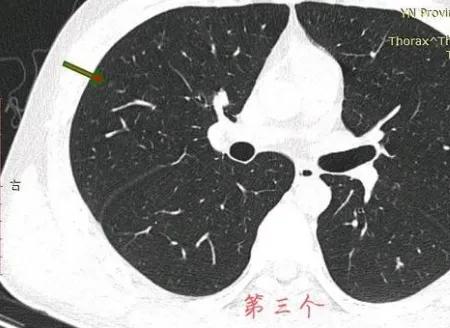

在11月16号,自己担心去了一趟胸外科门诊,医生看了片子之后直接让我复查胸部平扫➕HRCT,看了复查片子之后医生问过我也没有家族史,随后医生说癌症可能性非常大,并且已经说到要手术和靶向药治疗。但还是让我吃半个月莫西沙星,由于当地拜复乐没买到,就吃了其他牌子的莫西沙西,最后网购吃了三颗拜复乐!距离复查只有一周,这个月以来一直焦虑。因为双肺足足有四个磨玻璃结节,在网上看到戴主任的专业,希望能够得到戴主任的建议,4个结节冷月都帮我截图了,我放在下面,麻烦戴主任帮我看看!

今年我21岁,距离首次发现肺结节两个月左右,10月24日首次发现肺结节,11月16日去胸外科门诊,医生告知高危结节需要抗炎一个月后复查!期间得到您两次回复,告诉我大的结节已经有事,同时我加号请求您也说等抗炎结束再说!我昨天去复查,当时医生告诉我目前大的那个结节确定是恶性了需要立即手术,可能已经到浸润阶段!小的结节(结节三)感觉不太好,可能需要二次手术!

左肺结节,至少微浸润腺癌。右侧结节良性的。